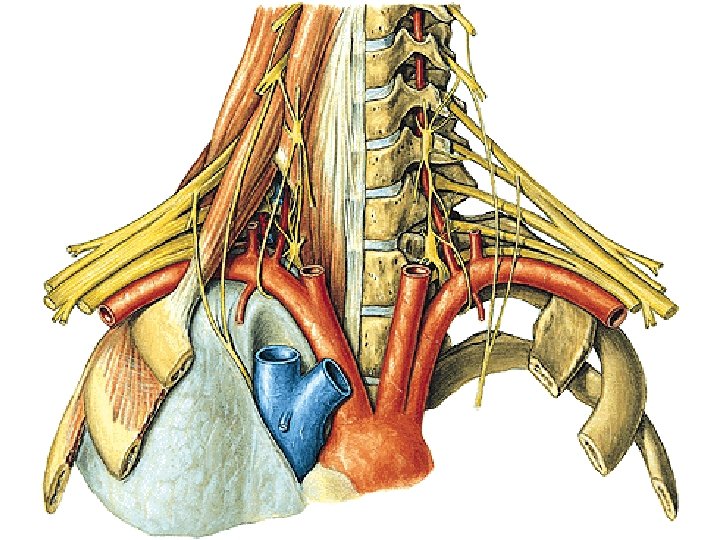

Nodi lymph. axillares: - laterales - pectorales (Sorgius) - subscapulares - centrales - apicales (infraclaviculares) tr. subclavius